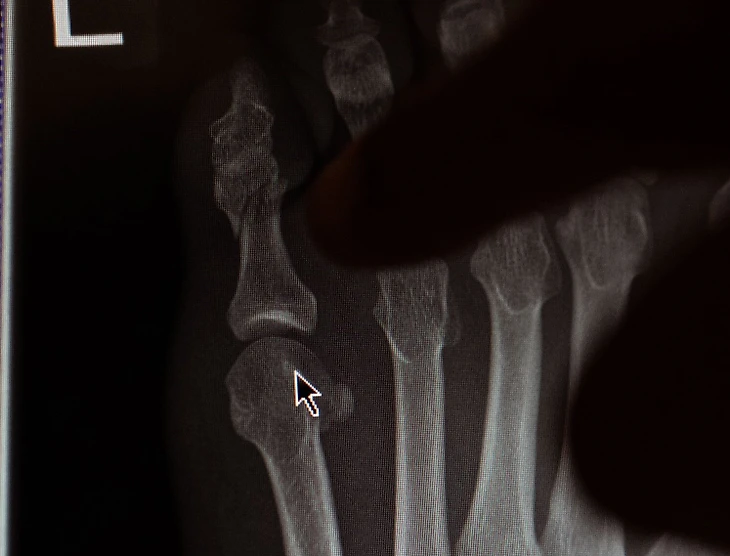

Конор Макгрегор снялся с боя против Майкла Чендлера из-за перелома пальца ноги.

Фотографиями травмы бывший двойной чемпион UFC поделился в социальных сетях.